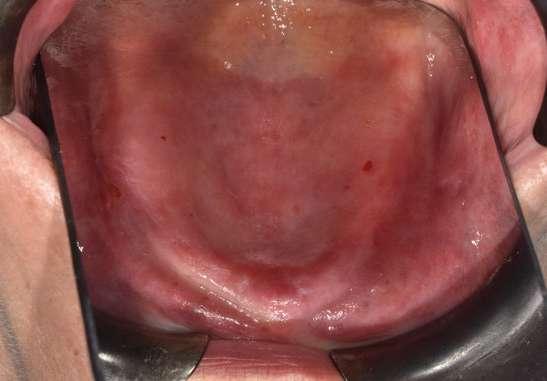

Por su parte, una exploración clínica exhaustiva nos permite elegir la técnica más adecuada para cada caso. Un síndrome de Kelly con reabsorción de la zona anterior nos llevará a usar membranas o sistemas con refuerzo de titanio para contrarrestar las fuerzas nocivas en la zona anterior. En el caso a tratar se observa una correcta altura anterior sin reabsorción de la premaxila suficiente para poner implantes en altura. (Figuras 1 y 2).

Por lo tanto, podremos usar membranas sin refuerzo de titanio tipo nativa (creos™ xenoprotect).

Con respecto al perfil facial, se debe ver el grado de reabsorción del paciente. Un perfil con mucha reabsorción precisa de algún tipo de regeneración para ganar volumen si queremos una prótesis estable en el tiempo y fija. En este caso hay una gran pérdida de volumen maxilar con inclinación de la nariz hacia abajo y cambio del plano oclusal (Figura 18). Esto nos decanta por una cirugía regenerativa en anchura anterior para mejorar la emergencia de la prótesis y la estética final. Podremos optar por ganar tejido blando con materiales sustitutivos (creos™ mucogain) o con regeneración ósea guiada con mezcla de hueso autólogo y xenoinjerto (creos™ xenogain).